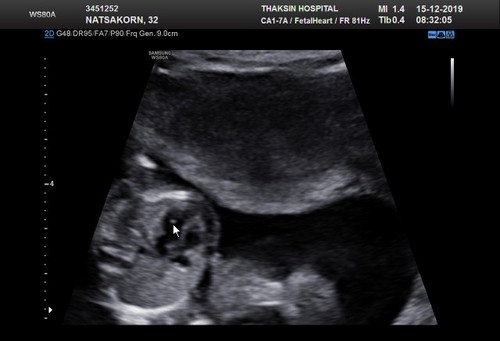

ท้อง 4 เดือน หมออัลตราซาวด์พบจุดสีขาวในหัวใจลูก แนะนำให้เจาะน้ำคล่ำตรวจ ใครเคยเจอแบบนี้บางค่ะ ลูกจะผิดปกติมั้ย เครียดมากเลย

เพื่อความสบายใจของคุณแม่นะคะ ที่อเมริกา มีการพบจุดขาวนี้ 1 ในทุกๆ 30 คน ส่วนใหญ่คลอดออกมาลูกแข็งแรงปกติดี ไม่มีผลกับสุขภาพของลูก ถ้าเคยตรวจ Nuchal Translucency หรือตรวจ Nifty แล้ว ก็หายห่วงได้เลย ไม่ได้เป็นตัวบ่งชี้ว่าเป็นดาวน์ แต่ถ้าไม่เคยตรวจหาดาวน์เลย หมออาจจะแนะนำให้ตรวจเลือดหรือเจาะน้ำคร่ำเพื่อความสบายใจ มันเป็นการสะสมของแคลเซียมที่หัวใจลูก บางทีจะหายไปเองภายใน 4-5 weeks หรือเด็กบางคนคลอดออกมาพร้อมจุดขาวนี้เลยแล้วมันจะหายไปเองตอนเด็กค่อยๆโตขึ้น จุดขาวนี้เริ่มพบได้มากขึ้นเพราะรูปอัลตราซาวด์มันชัดขึ้น เรียก EIF นะคะ หรือ Echogenic focus